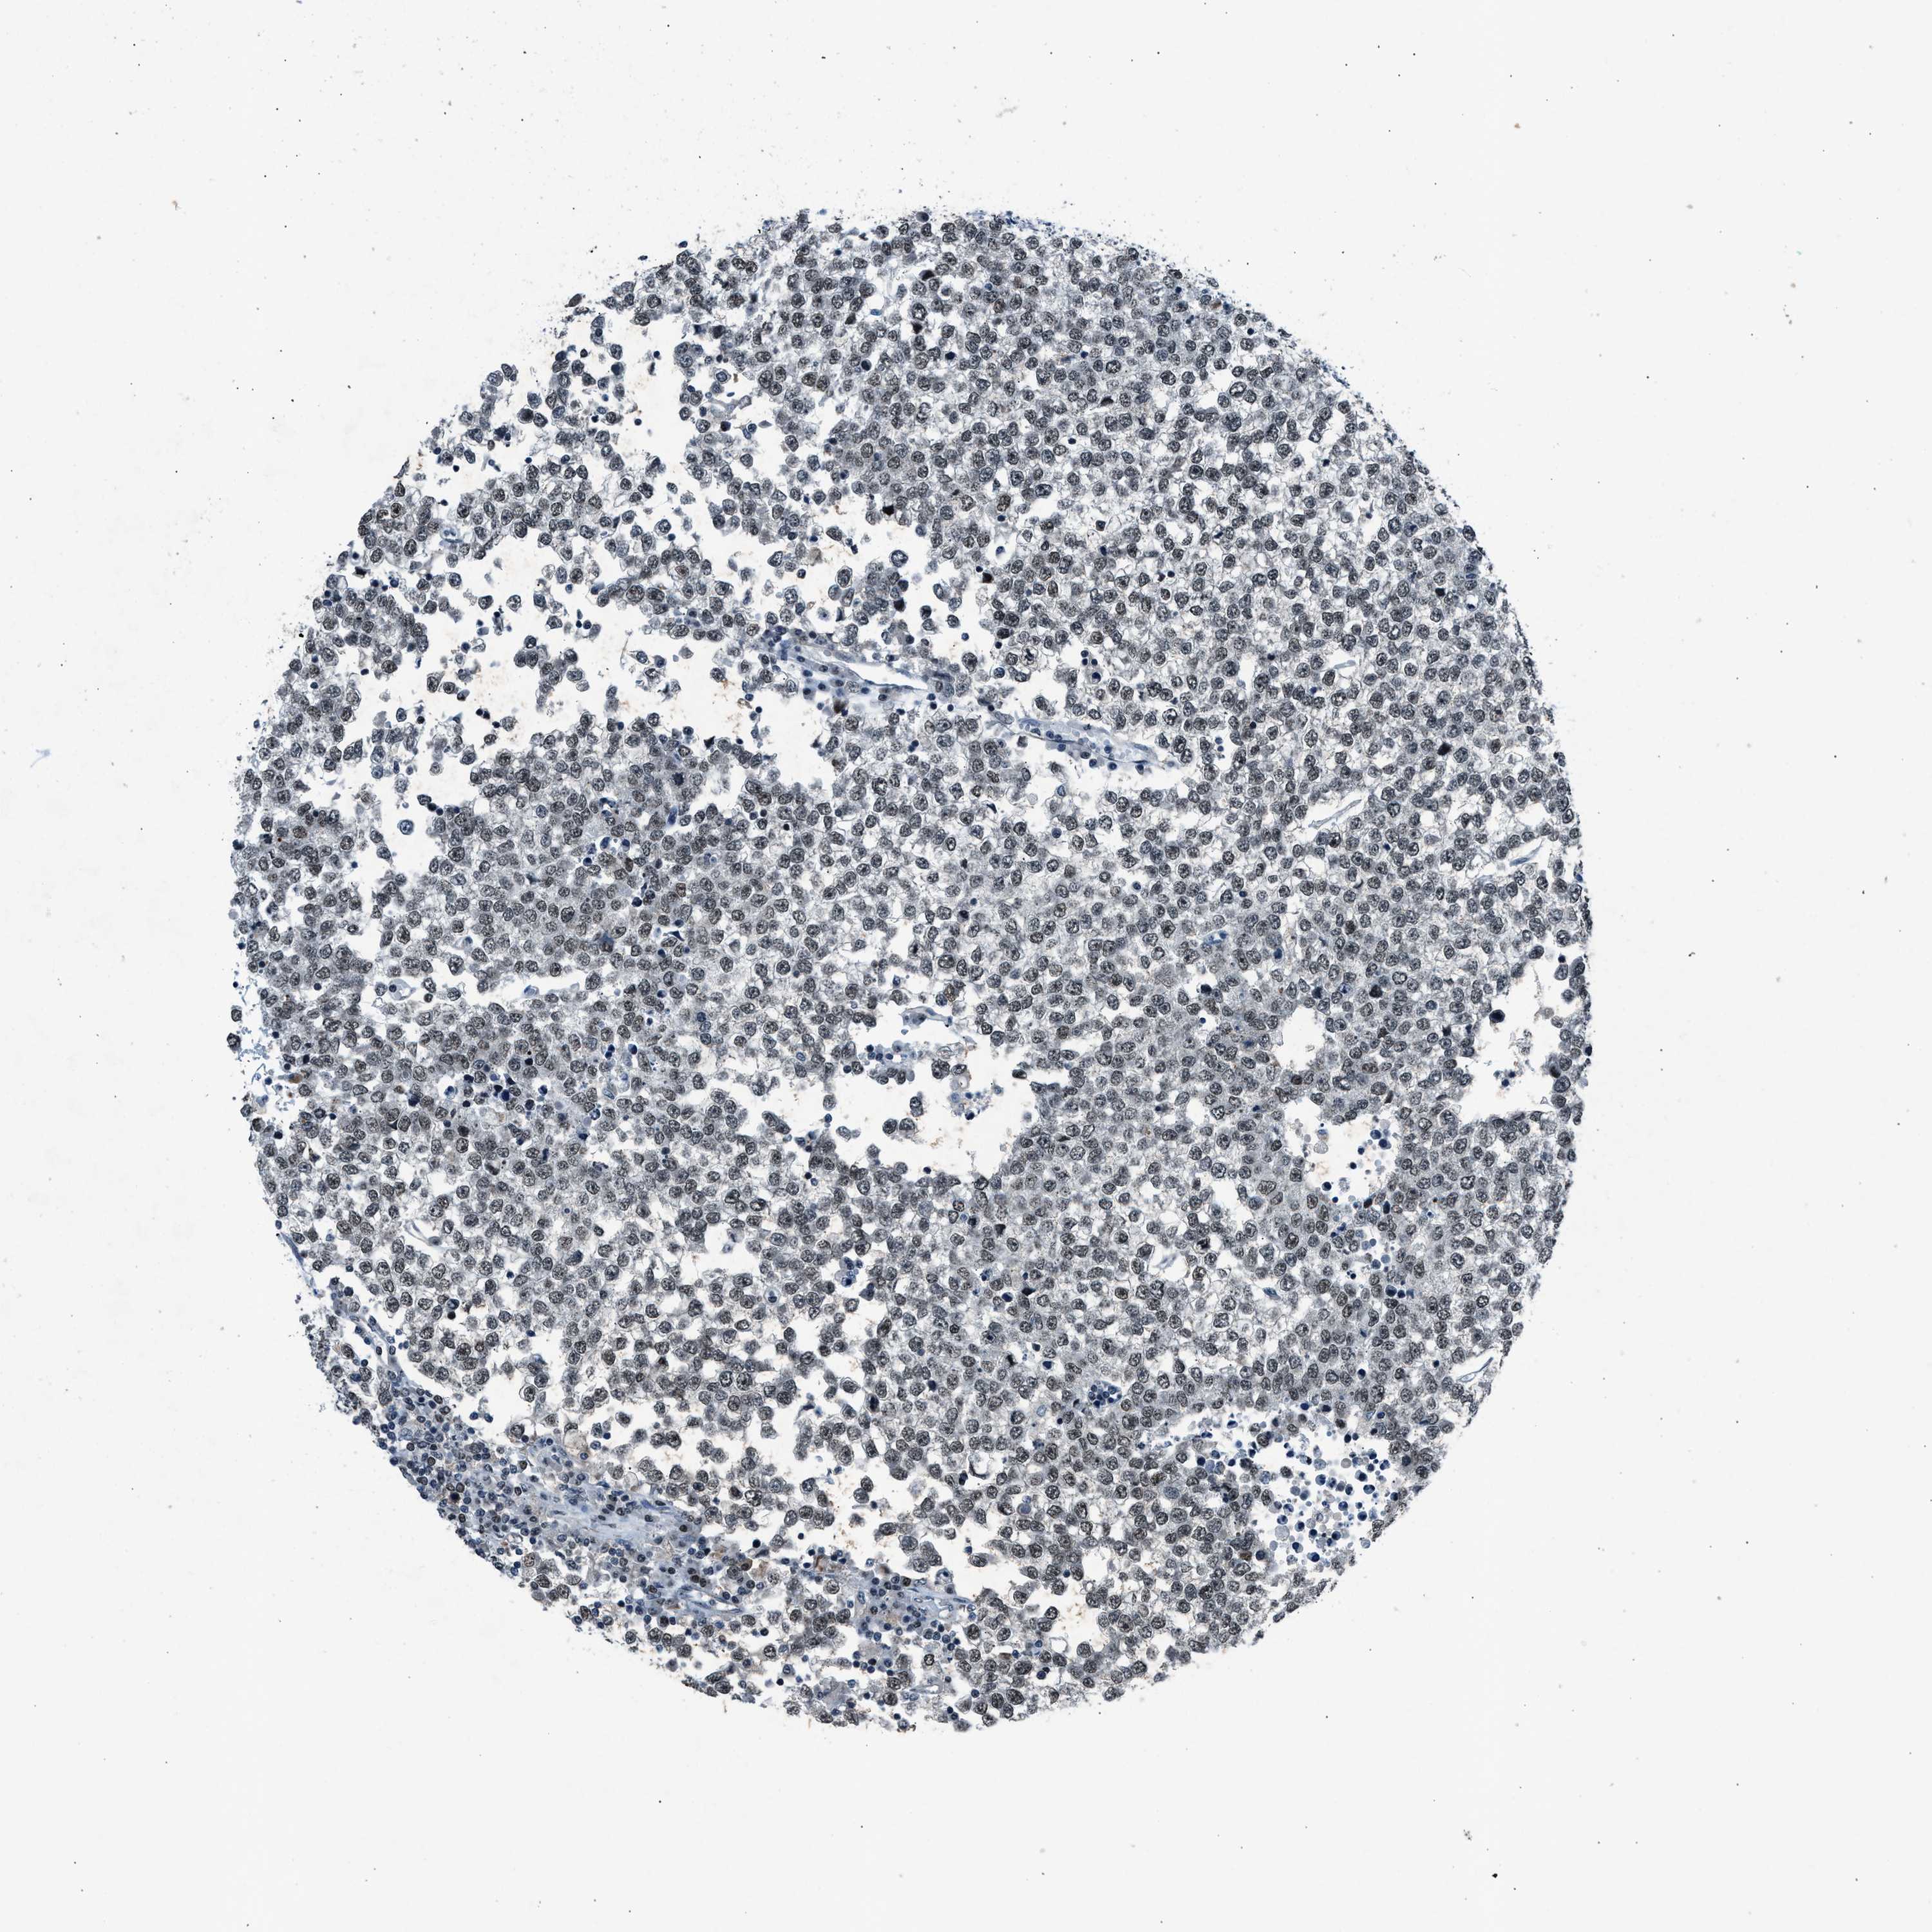

TESTIS CANCER - Protein expressioni

A mouse-over function shows sample information and annotation data. Click on an image to view it in a full screen mode. Samples can be filtered based on level of antibody staining by selecting one or several of the following categories: high, medium, low and not detected. The assay and annotation is described here.

Note that samples used for immunohistochemistry by the Human Protein Atlas do not correspond to samples in the TCGA dataset.

Antibody stainingi

Antibody staining in the annotated cell types in the current human tissue is reported as not detected, low, medium, or high, based on conventional immunohistochemistry profiling in selected tissues. This score is based on the combination of the staining intensity and fraction of stained cells.

Each image is clickable and will lead to virtual microscopy that enables deeper exploration of all samples and also displays staining intensity scores, fraction scores and subcellular localization as well as patient and tissue information for each sample.

Antibody CAB018364

Staining

High

Medium

Low

Not detected

Intensity

Strong

Moderate

Weak

Negative

Quantity

>75%

75%-25%

<25%

None

Location

Nuclear

Cytoplasmic/membranous

Cytoplasmic/membranous,nuclear

Carcinoma, Embryonal, NOS

Seminoma, NOS